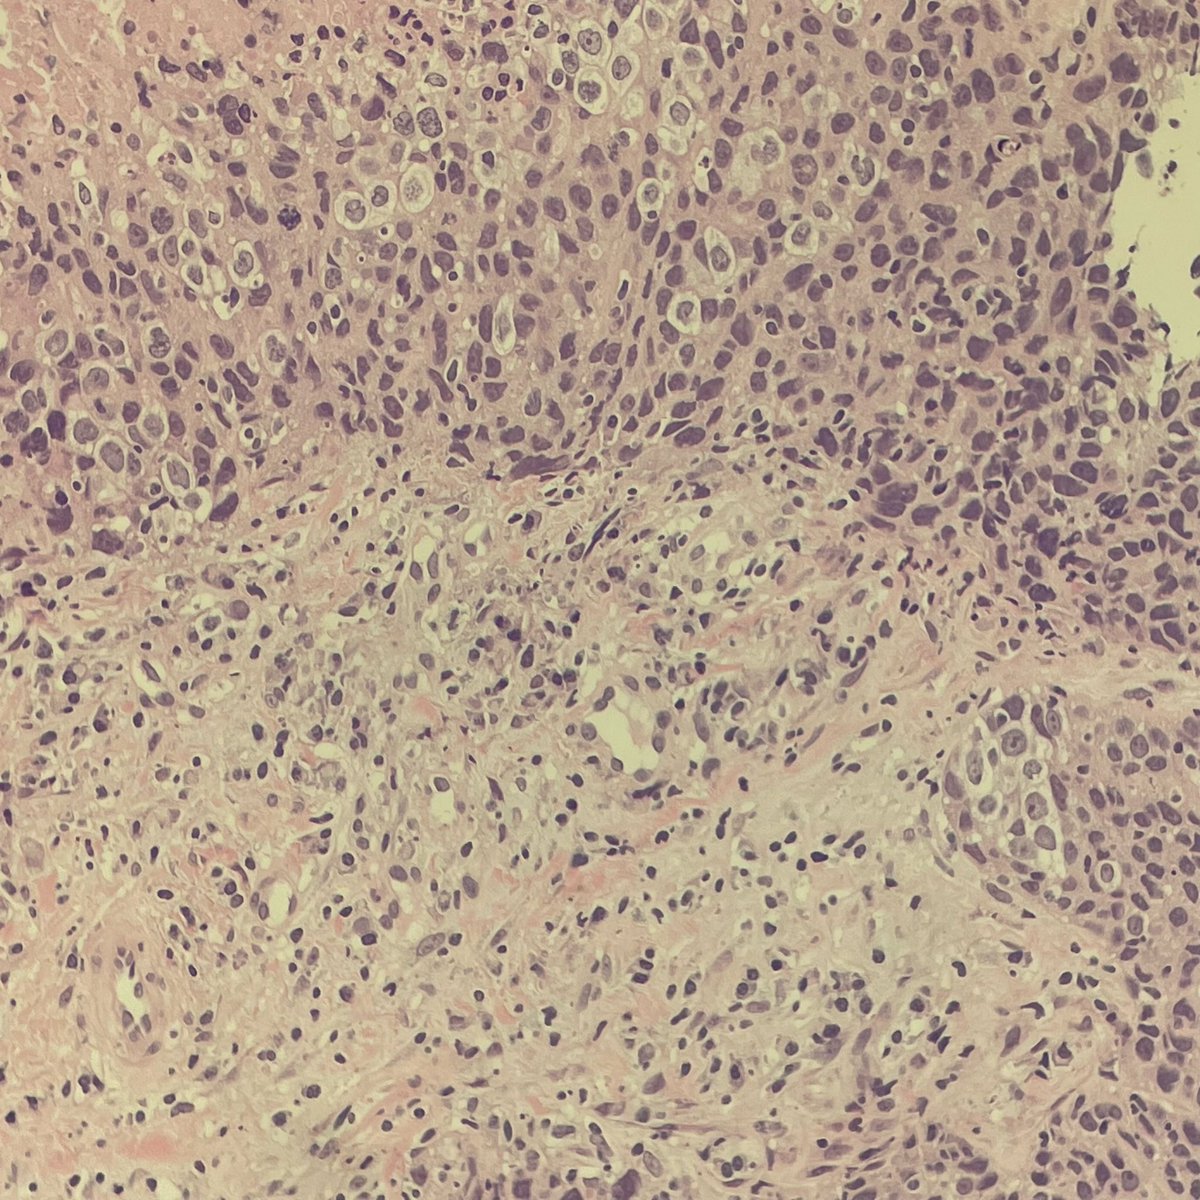

Pilomatrix-like High Grade endometrioid Adenocarcinoma of the ovary 1. Basaloid nests 2. Necrosis 3. Abrupt keratinization 4. Ghost “ shadow” cells